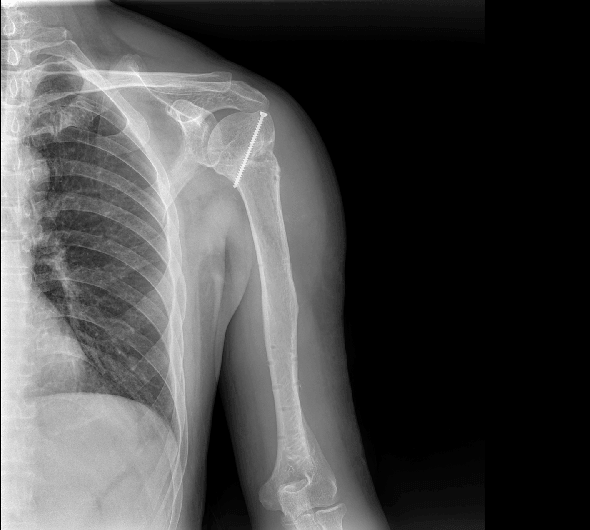

原厂优质影像链,搭载直接生长式碘化铯非晶硅平板,带来更加清晰锐利的图像效果。